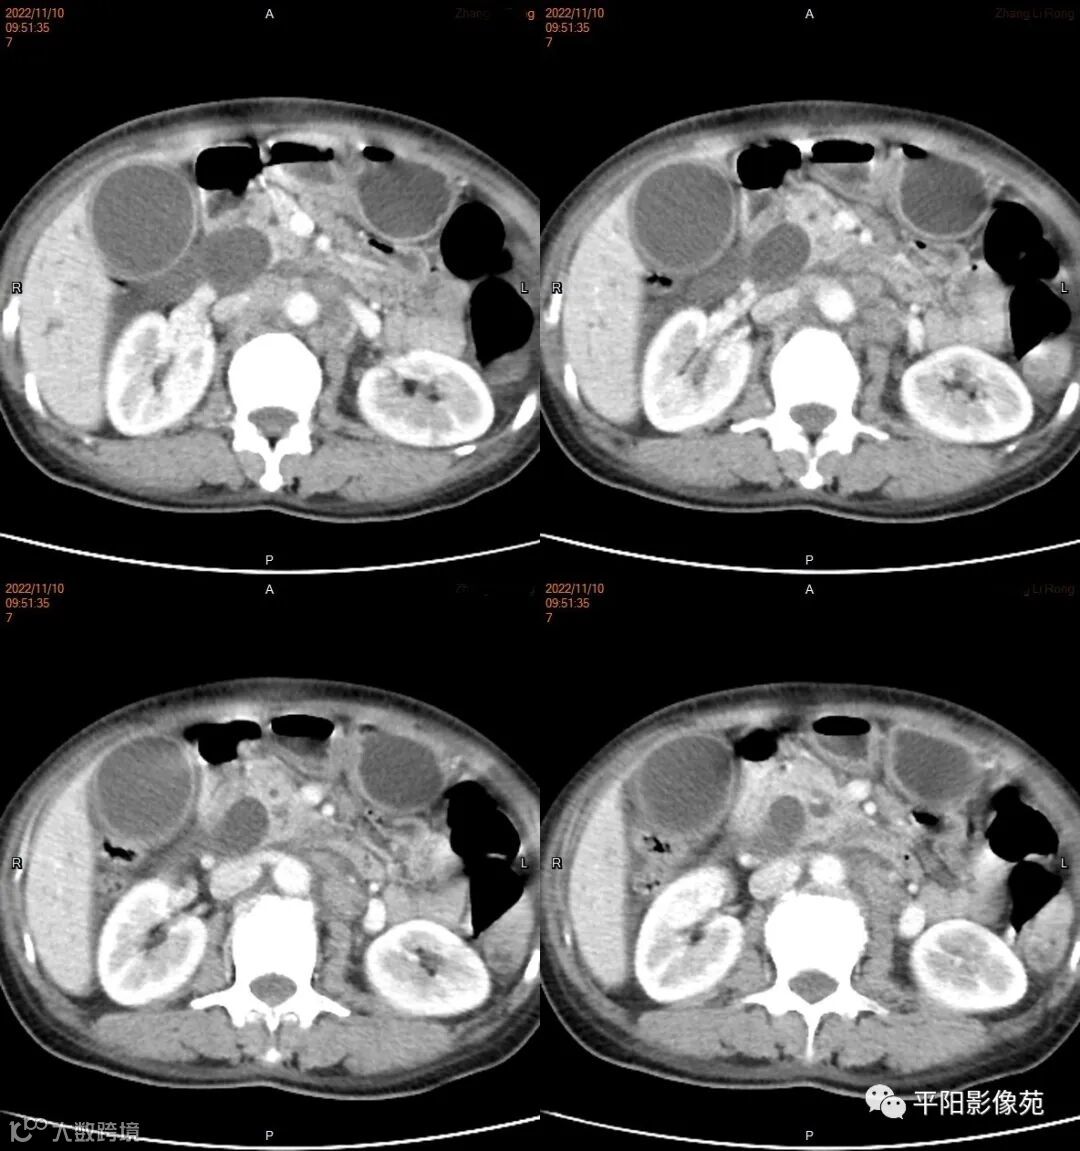

影像学检查

CT

影像表现: